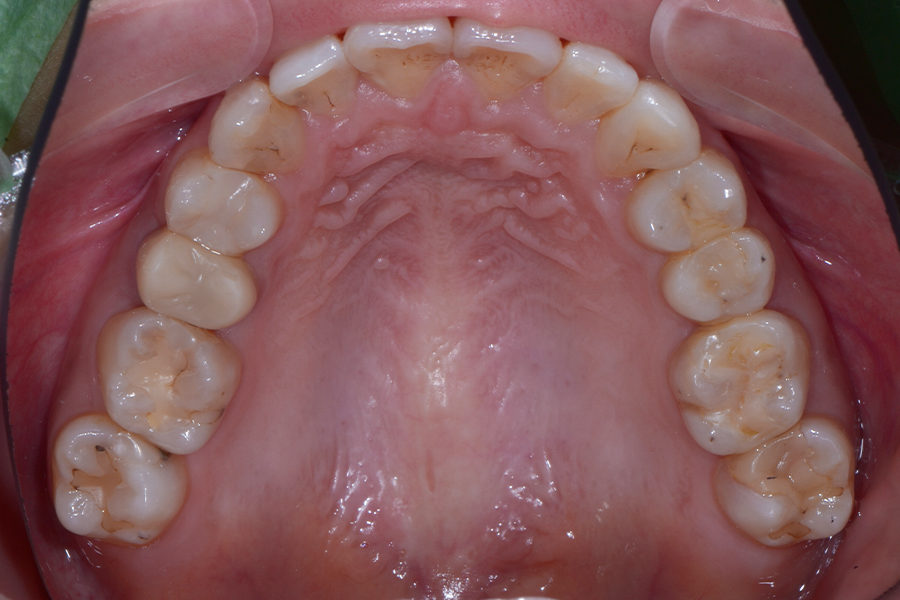

• 治療前